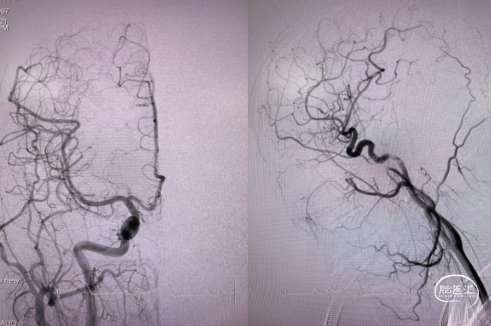

4、经Marksman™ 微导管输送Pipeline™ Flex 血流导向密网支架 375-35,准确输送到位后,开始释放Pipeline™ Flex 血流导向密网支架。

5、使用推拉结合方法继续缓慢释放Pipeline™ Flex 血流导向密网支架,确保支架远端和中动脉贴壁良好,再向前推挤支架使可见中间导管自动向近段移位,间断予以释放中间导管张力后,再使用前诉方法释放支架,确保支架与载瘤动脉良好贴壁。

6、支架释放至覆盖瘤颈约1/2处,继续经Echelon™ 10微导管填入多枚弹簧圈,给予支架充足的支撑力后,继续使用推拉技术释放支架,最后支架近段着陆于左侧大脑中动脉M1段。

7、动脉瘤内继续填入弹簧圈将动脉瘤致密填塞,正位造影观察大脑中动脉血流通畅。